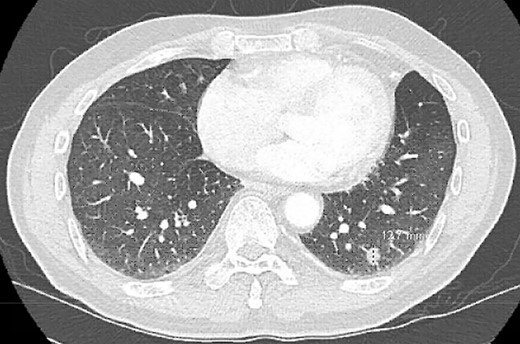

A 68-year-old male, current smoker with chronic cough and night sweats was diagnosed with a suspicious 13 mm spiculated left lower lobe nodule (Fig. 1). His medical history included a 35+ pack-year smoking history, treated tuberculosis, hypertension, peripheral vascular disease, aortic atherosclerosis and asthma with severe chronic obstructive pulmonary disease (COPD) managed on low-dose steroid taper. Pulmonary function testing and positron-emission tomography (PET) demonstrated a forced expiratory volume (FEV1) of 40% with mildly PET-avid disease. The patient underwent VATS left lower lobe wedge resection of the left lower lobe nodule with mediastinal lymph node sampling. Extensive anthracosis and adhesive disease was seen. Pathology revealed benign parenchyma with fibrinous changes and organizing pneumonia.